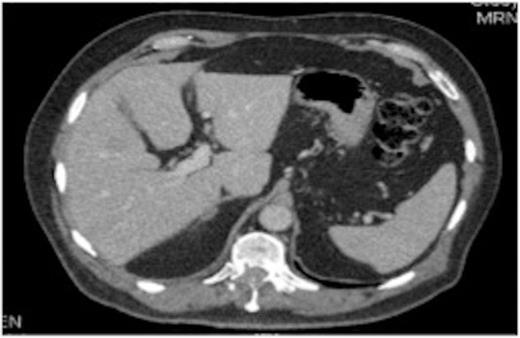

A 63-year-old man presenting with right upper quadrant pain was, following a CT of the chest, abdomen and pelvis, found to have a lesion in the lung and multiple liver metastases.

Original thoracic CT scan, which was performed 2 months prior to the MRI, shows the spinal metastasis

On review of the original thoracic CT scan, which was performed 2 months prior to the MRI, the tumour was distinguishable but, as the spine is such a rare location for carcinoid metastasis, it was initially unreported.